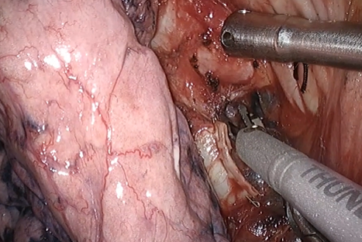

呼吸器外科手術(単孔式)単孔式 左肺上葉上大区域切除</br><富山大学附属病院 本間崇浩先生>

呼吸器外科手術(単孔式)単孔式 胸腺切除術</br><藤田医大 岡崎医療C 須田隆先生>

呼吸器外科手術(単孔式)単孔式右肺上葉切除+縦隔リンパ節郭清</br><藤田医大 岡崎医療C 須田隆先生>

呼吸器外科手術(単孔式)単孔式 縦隔腫瘍切除</br><近畿大学病院 千葉眞人先生>

呼吸器外科手術(単孔式)単孔式 右肺上葉切除</br><近畿大学病院 千葉眞人先生>